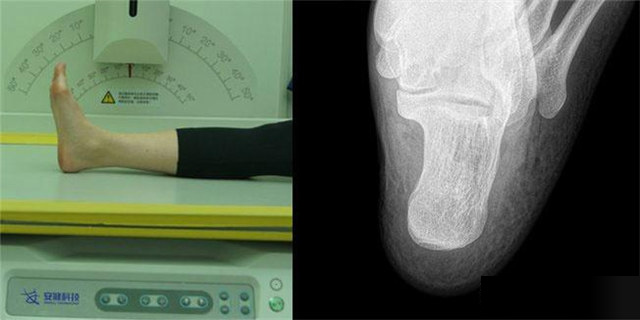

下肢:脛腓骨、踝、足脛腓骨長骨檢查需要包括--側的關節(jié)踝關節(jié)常規(guī)正+外側位,特殊時可選內(nèi)斜位足常規(guī)前后正位+內(nèi)斜位,外傷鑒定等情況,需要負重的水平側位(包括足尖和足跟)跟骨側位+軸位